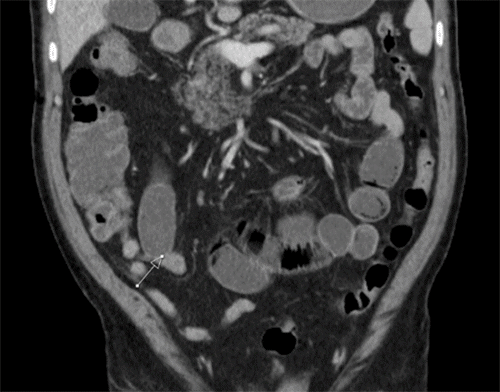

The patient again presented to the ED one month after surgery with recurrent symptoms. Imaging showed dilated small bowel with a similar appearance to the prior CT (Figure 2). The decision was made to manage the patient with exploratory laparotomy due to his multiple failures with more conservative management. Upon running the bowel, a subtle transition point was noted in the jejunum (Figure 3). After opening this portion of bowel on the back table, a circumferential band-like structure could be palpated within the bowel wall (Figure 4). Pathological evaluation of this tissue showed circumferential submucosal fibrosis with mucosal tethering, but no definitive stricture or diaphragm was identified (Figure 5). Postoperatively the patient was counseled about the likelihood of recurrence if he continued his NSAID therapy. Diclofenac has been discontinued though the patient remains on low-dose aspirin due to cardiac risk. The patient's postoperative course was uneventful. He has had no recurrence of obstructive symptoms since this intervention occurred about one and a half years prior at the time of this writing.

Figure 2. Coronal CT Scan from Latter Presentation. Published with Permission

Transition point in similar position as prior (marked by arrow).